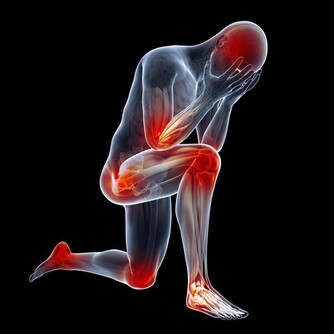

陳 昌平說明大腸癌的成因:「簡單說,是先有便祕,接著產生息肉,再病變成大腸癌。」大腸是由升結腸、橫結腸、降結腸及乙狀結腸等所構成,左側的大腸管徑比右 側大腸窄,當有腫瘤發生時,就會出現腸阻塞而引起便祕、腹脹甚至腹痛的情形。因為糞便大多在左側的結腸成形,因此如果阻塞的狀況嚴重的話,所排出的糞便就 會有時還會參雜血絲, 嚴重到便祕及解血便情形。

運動可加速大腸的蠕動,縮短糞便通過大腸的時間,降低大腸內膜接觸糞便時間。適量的運動,如每星期3次快走、每次30分鐘以上,有助減低罹患大腸癌的機會。